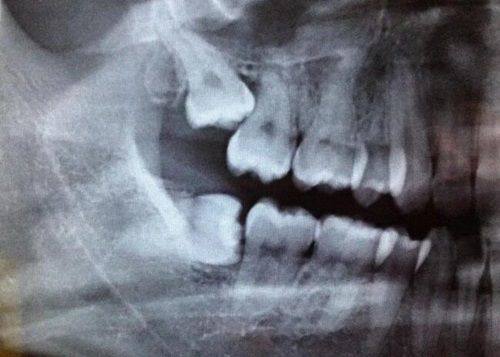

南通摩尔口腔医院紧跟口腔医学发展潮流,引进了精良的口腔诊疗设备。在牙齿矫正方面,采用了精良的数字化矫正技术,能够精细分析牙齿情况,制定个性化的矫正方案,矫正成效显著且时间相对较短。在种植牙领域,运用了精良的种植系统,提高了种植的成功几率和稳定性。

在牙齿矫正方面,医生们能够根据患者的不同情况,如牙齿排列不齐、咬合不正等,制定个性化的矫正方案。无论是传统的金属矫正还是隐形矫正,都能达到理想的成效。在种植牙领域,医生们熟练掌握各种种植技术,能够正确地将种植体植入牙槽骨内,提高种植的成功几率。